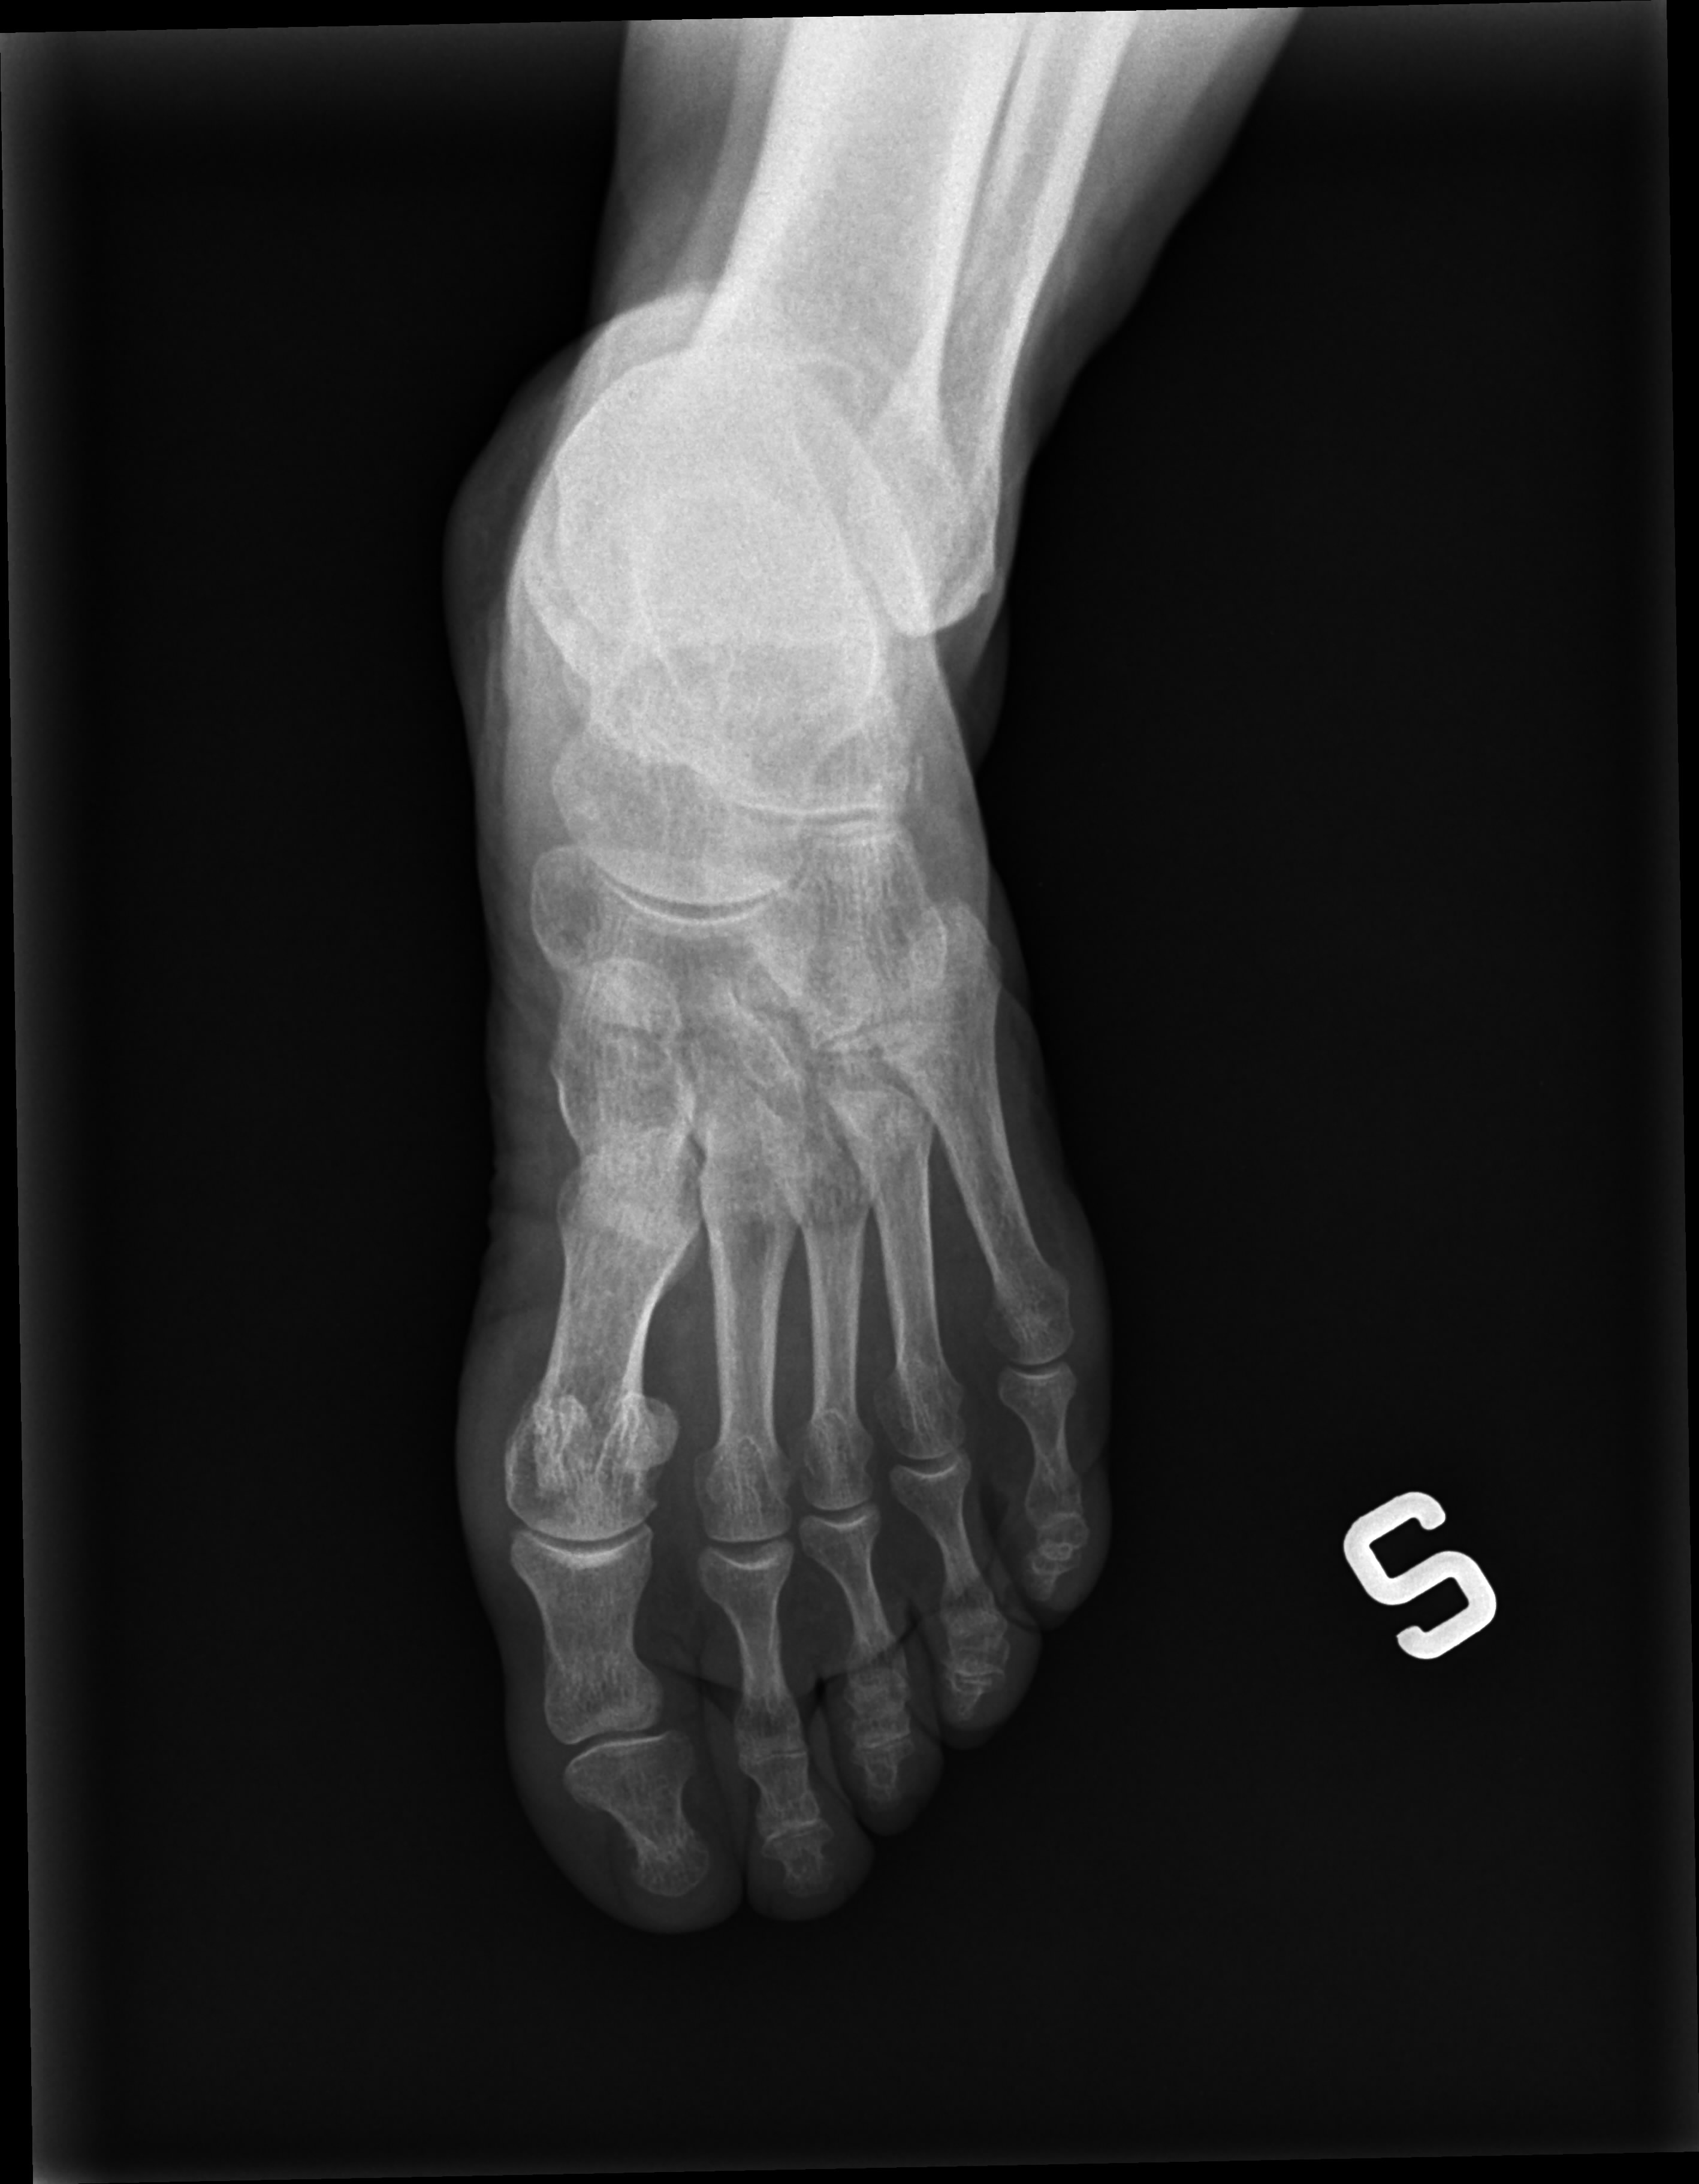

Buona sera vorrei una consultazione delle lastre che allego

per sapere se ho rotture ossee al piede .Saluti Rosi

2_0885653618r.aup.jpg

[ 426.55 KiB | Osservato 596 volte ]